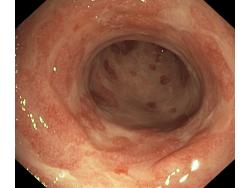

Zapalenie wrzodziejące jelita grubego